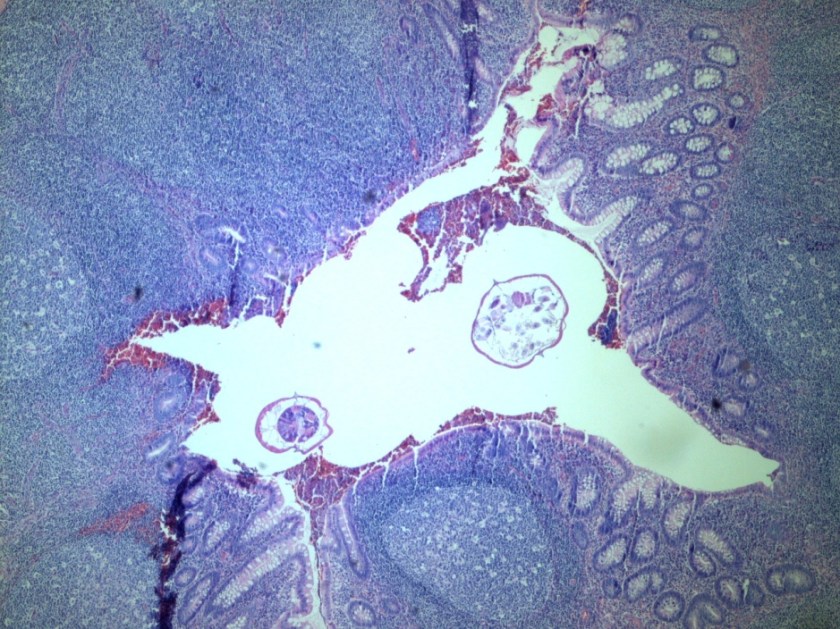

Image 1. Cross section of appendix containing two intra-luminal helminths (H & E stain).

Enterobius vermicularis (human pinworm) is an intestinal nematode (roundworm) with a worldwide distribution that is most prevalent among school-age children. Cross sections of the nonsegmented, cylindrical worms demonstrate a well-developed digestive tract, reproductive system, and two lateral alae (Images 1-3). E. vermicularis has two sexes and Image 1 demonstrates that the male is smaller than the female. Humans are directly infected upon ingestion of E. vermicularis eggs (fecal-oral route of transmission). The eggs then hatch and immature worms undergo maturation within the human gastrointestinal tract (Image 1). Eggs are shed in stool and the typical E. vermicularis eggs (Image 2) are thick-shelled with one flattened aspect, described as “D-shaped”. Patients with the infection are commonly asymptomatic or may complain of perianal pruritus. Rarely, patients present with abdominal pain secondary to E. vermicularis-associated acute appendicitis (1).